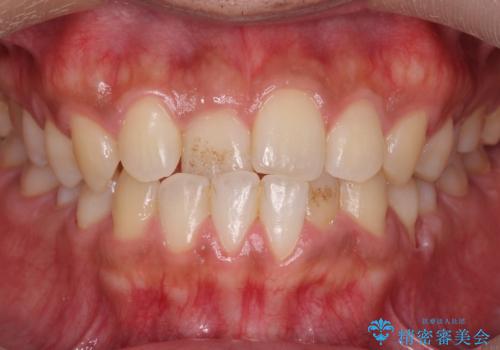

【非抜歯】インビザラインで正しい噛み合わせを

【非抜歯】インビザラインでガタつきと口元を改善!非抜歯でも印象が変わる矯正治療